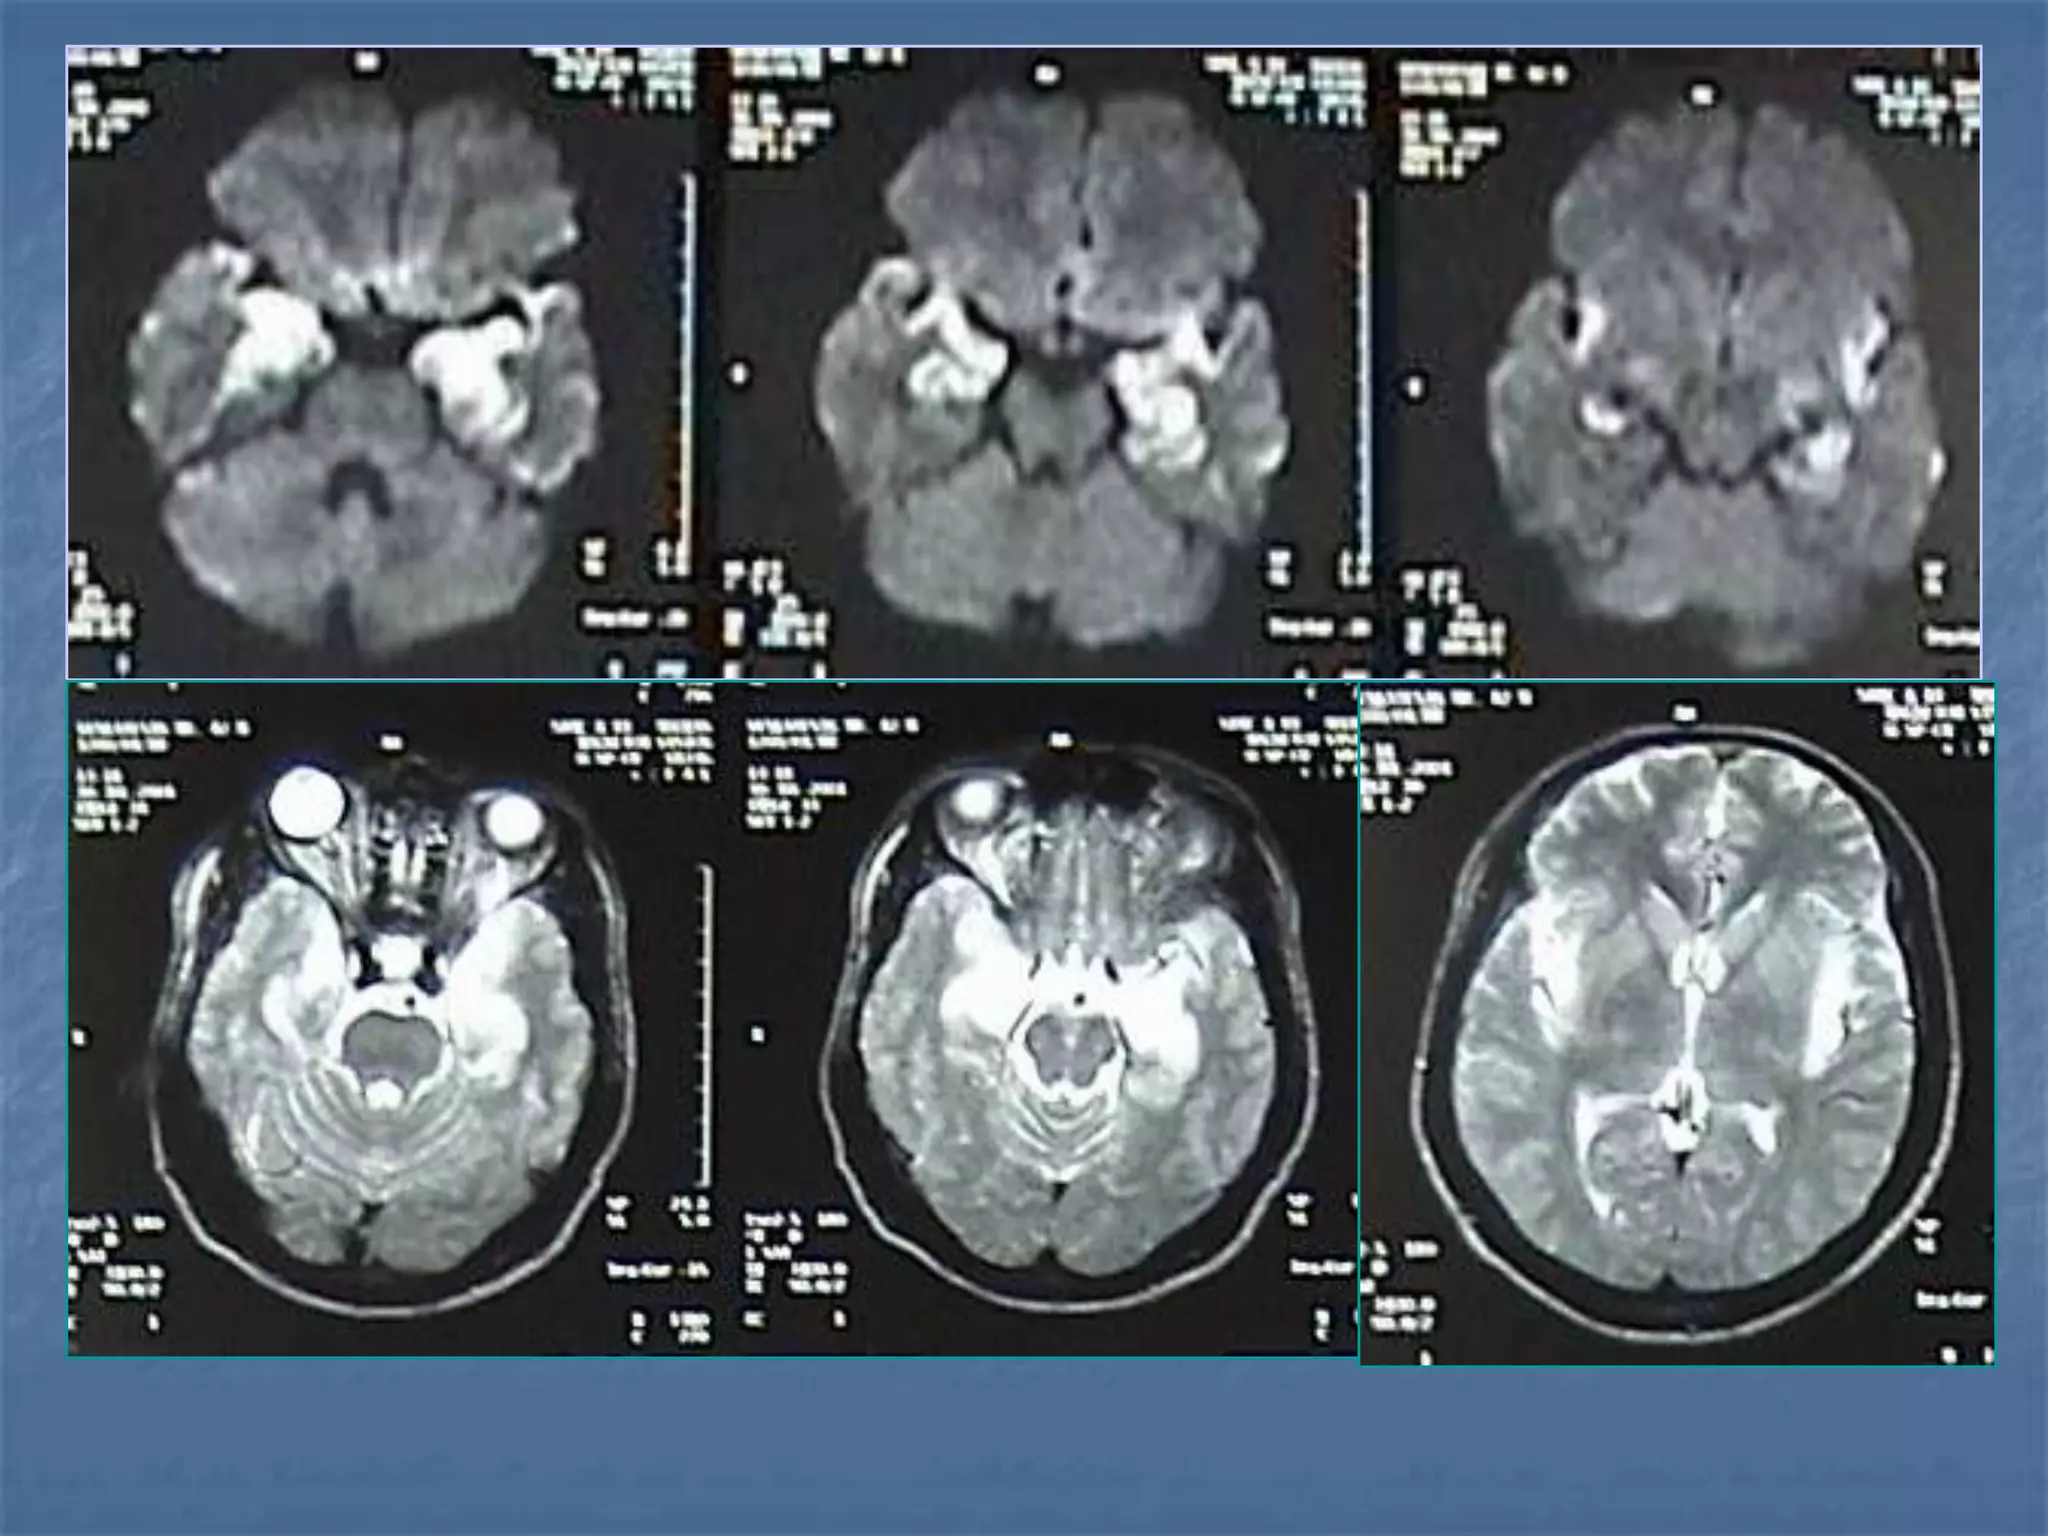

Diffusion Weighted Imaging

Radiology 2000;217:331-345

Detects Infarct As

Early As 15-30

minutes

AJNR 2003 ;24:878-885

• 46 patients with acute stroke

• CT and DWI within 6 hours

• Mean delay 24.5 min. (R 10–41 min.)

• EIC on CT - 33/46 (Sn 73%)

• DWI 42/45 - (Sn 93%)

CT vs DWI